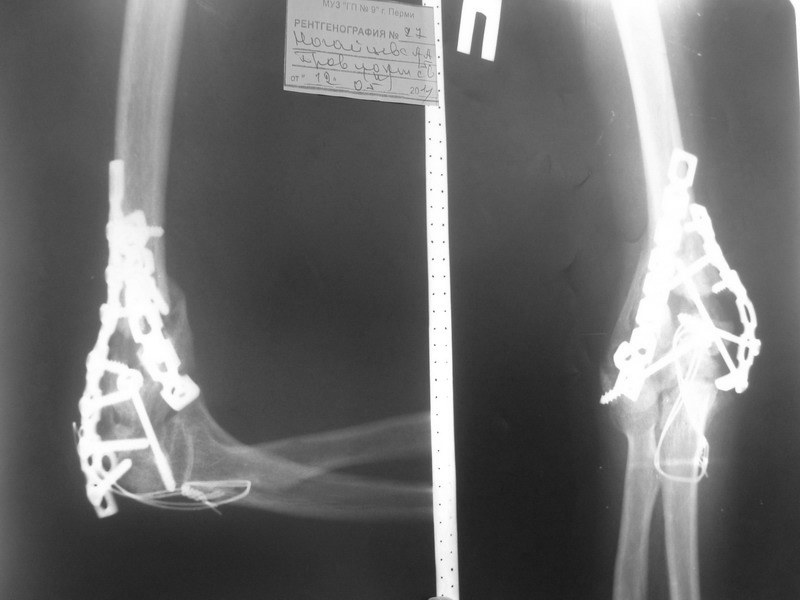

На томографе от 09.2011 - вялая консолидация перелома плеча и локтевого отростка. на томографе от 02.2012 - картина схожая - вялоконсолидирующийся перелом правого плеча, вялоконсолидированный перелом локтевого отростка, угловая деформация по типу варусной. Контрактура локтевого сустава - сгибание 100, разгибание 80, супинация 45, пронация 40.

В наших планах выполнить костную пластику с удалением реконструктивных пластин и с установкой LCP пластин, есть ли смысл в остеотомии для коррекции варуса?. И будет ли смысл в этом. Хотелось бы увеличить амплитуду движений в суставе. Реально ли это на фоне такой картины?. Заранее спасибо

Имя     : AP 02.12 800.jpg

Тип     : image/jpg

Размер  : 61358 байтов

Описание: отсутствует

Url     : http://weborto.net:8080/pipermail/ortho/attachments/20120313/c909356e/attachment-0008.jpg